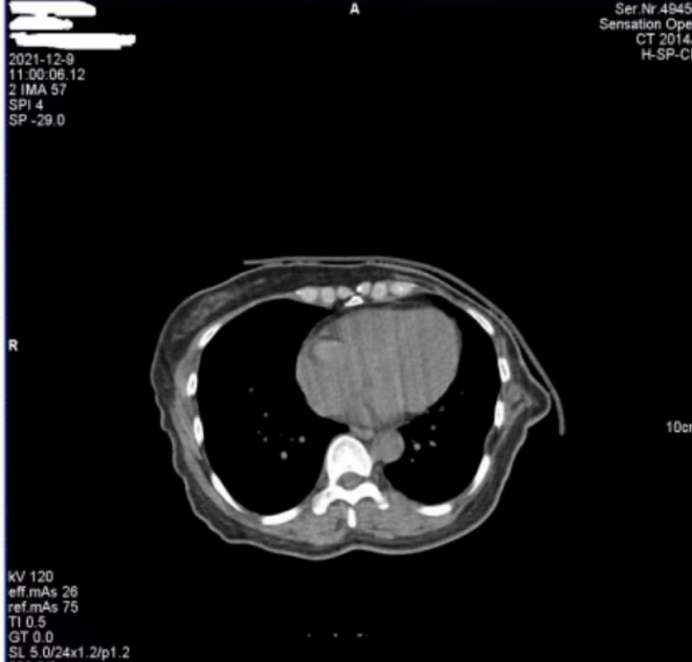

醫(yī)院反映,西門子Definition型CT機(jī)在進(jìn)行患者掃描時(shí),圖像上會(huì)偶發(fā)兩種偽影。一種是斜線狀偽影(圖 1),另一種是中心不規(guī)則高密度偽影(圖 2)。其中,斜線狀偽影對(duì)診斷影響較大,時(shí)常導(dǎo)致醫(yī)生無(wú)法準(zhǔn)確判斷患者病灶情況,醫(yī)院希望我們盡快排查并解決問(wèn)題。

圖1

對(duì)于圖 1 中的斜線狀偽影,我們第一時(shí)間查看了設(shè)備的錯(cuò)誤日志和球管歷史記錄,然而并未發(fā)現(xiàn)球管存在打火情況的相關(guān)信息。但仔細(xì)觀察圖 1 中的 S35C0,結(jié)合我們多年的維修經(jīng)驗(yàn),這一參數(shù)特征明確指向在當(dāng)時(shí)的掃描曝光時(shí)刻,球管存在打火現(xiàn)象。球管打火會(huì)直接干擾射線的穩(wěn)定輸出,進(jìn)而在圖像上形成這種斜線狀偽影,這也解釋了為何該偽影會(huì)對(duì)診斷造成較大影響。

綜合以上分析,圖 1 中的斜線狀偽影由球管打火引起,且已嚴(yán)重影響診斷;圖 2 中的中心偽影雖成因未完全確定,但推測(cè)與球管內(nèi)部雜物有關(guān)。鑒于球管打火問(wèn)題的嚴(yán)重性以及兩種偽影可能存在的關(guān)聯(lián)性,我們判斷需要更換球管來(lái)徹底解決問(wèn)題。

此次維修案例中,更換球管后兩種偽影均消失的結(jié)果,不僅證實(shí)了圖 1 中斜線狀偽影由球管打火導(dǎo)致的判斷,也驗(yàn)證了我們對(duì)圖 2 中心偽影成因的推測(cè)是正確的,即球管內(nèi)部雜物在油路循環(huán)過(guò)程中,于曝光時(shí)處于出射線位置而造成了中心偽影。